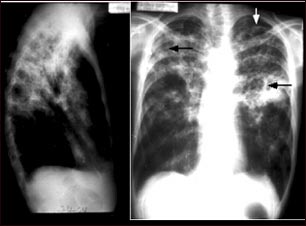

Tuberculosis avanzada, radiografía de tórax

La tuberculosis es una enfermedad infecciosa que causa inflamaciones, formación de tubérculos y la aparición de otras expansiones tisulares que pueden causar necrosis tisular. Estas radiografías de tórax muestran una tuberculosis pulmonar avanzada en la cual se observan varias áreas claras (opacidades) de diferentes tamaños, unidas unas con las otras (coalescencia). Las flechas señalan la localización de las cavidades de estas áreas claras. La radiografía de la izquierda muestra claramente que las opacidades están localizadas en el área superior de los pulmones, vistas desde la parte posterior. Esta es la apariencia típica de la tuberculosis pulmonar crónica, pero también puede ocurrir en la histiocitosis pulmonar crónica y en la coccidioidomicosis pulmonar crónica. La tuberculosis pulmonar está reapareciendo nuevamente con una mayor resistencia que la hace difícil de tratar; la tuberculosis pulmonar es la forma más común de la enfermedad, aunque otros órganos también pueden ser infectados.